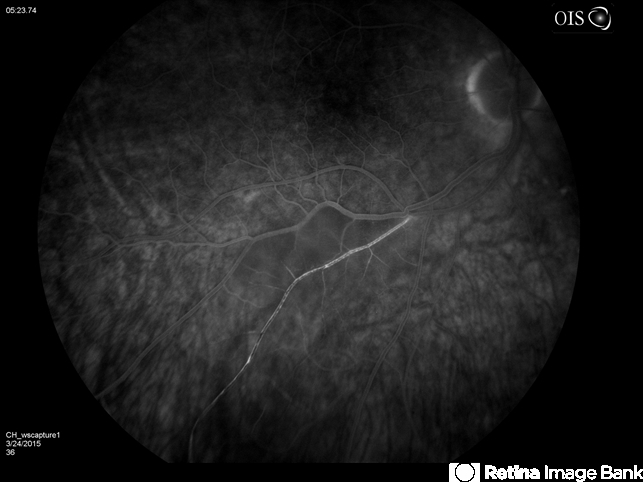

Your timing and focus of this BRAO Angiogram of this patients right inferior field is 'spot on'. Thank you for your excellent submission!

- branch retinal artery occlusion (BRAO), hollenhorst plaque

- Branch retinal artery occlusion with a Hollenhorst Plaque.